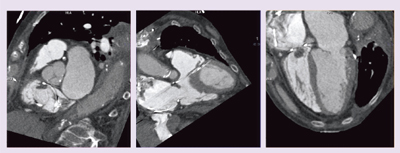

●症例1:狭心症

狭心症の診断のため64MDCTで撮影し,1年間の薬物療法後にFlash Spiral Cardioでフォローアップした症例を示す(図3,4)。図3のように,画質は治療前後でほぼ同等であるが,Flash Spiral Cardioでは実効線量と造影剤量が圧倒的に軽減できている。

図4は,Flash Spiral Cardioで撮影したCPR画像である。CT値がわずかに上昇していることから薬物治療の効果が見られたが,狭窄度はあまり変化がなかったことから,経過観察となっている。

![]() 図3 症例1:64MDCTとDefinition Flash (Flash Spiral Cardio)の比較 |

![]() 図4 症例1:Flash Spiral CardioのCPR画像 |